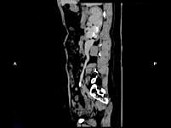

- 多项选择题女,44岁, 突发性胁腹部绞痛并向会阴部放射伴血尿一次,CT扫描如图所示, 下列说法正确的是 ( )

A、右侧肾盂肾盏扩张

B、右输尿管中上段扩张

C、右输尿管内可见沿输尿管走行的高密度影

D、右输尿管结石

E、左肾输尿管未见异常